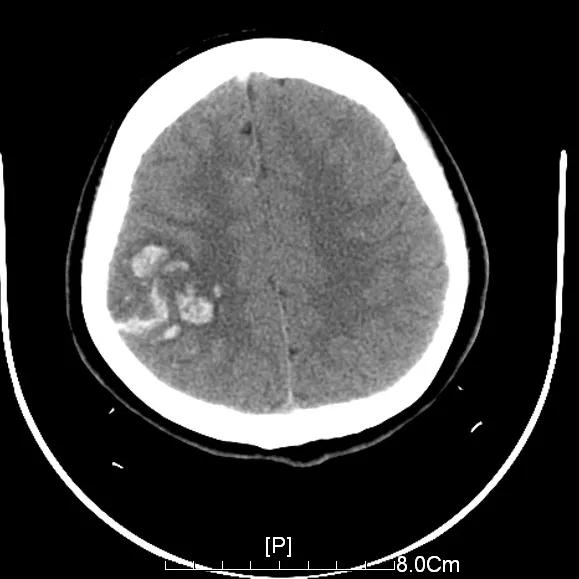

入院的相关检查发现,玲玲的头颅皮层下有出血,医生怀疑是静脉窦血栓引起的脑出血。后经静脉窦成像检查,明确是上矢状窦堵塞了三分之二。

▲玲玲的右侧顶叶皮层散在出血

一般颅内出血需要止血药物治疗,可当时玲玲的顶叶血肿使用止血药物,不但起不到止血作用,还会加重静脉窦血栓,导致出血增加。